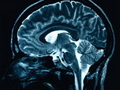

MRI scans show that carriers, even whose brains were at rest, showed intense activity in the hippocampus–that brain’s memory center–compared to non-carriers. Eventually, the hippocampus fries itself out from exertion leaving fertile conditions for Alzheimer’s to set in.